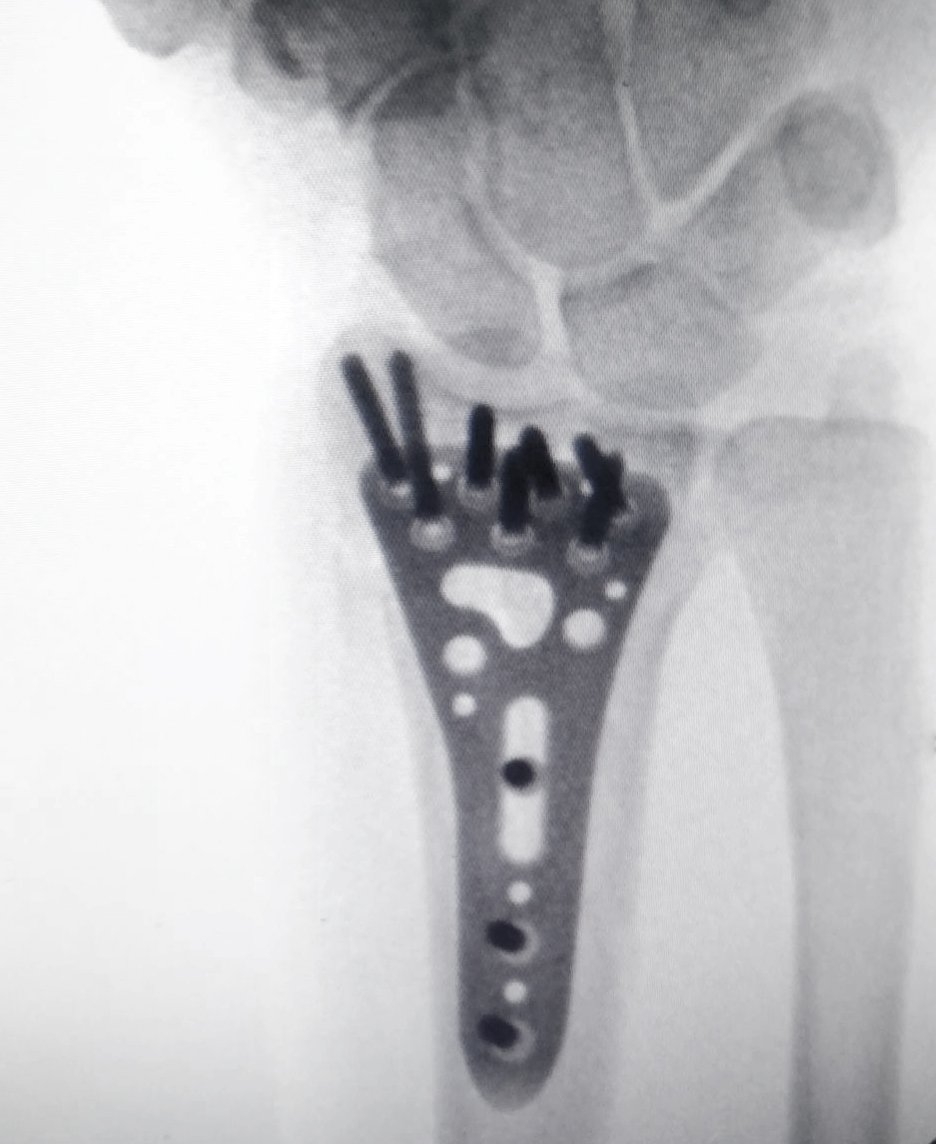

Hofer titanium locking plate system for fracture fixation Hofer titanium plate distal radius fracture fixation X-ray

Anatomical Precision

Hofer Osteosynthesis

💎 StickFIT Tech 🛡️ Anti-Corrosion

Low-profile titanium plates with patented StickFIT technology for superior fracture fixation.